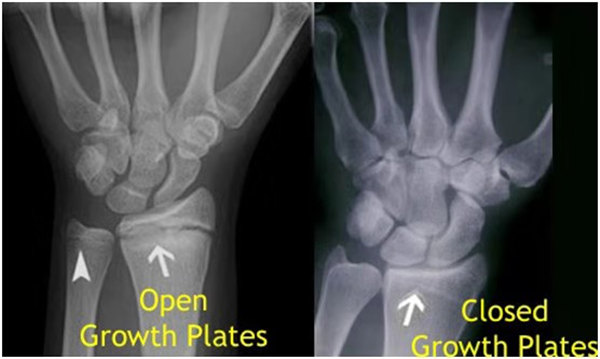

其實(shí)想要了解孩子的生長發(fā)育情況或者說孩子未來身高的趨勢,測骨齡是個好辦法。臨床上通常拍攝兒童的左手正位X光片 , 采用《中華-05》骨齡標(biāo)準(zhǔn)對手腕骨發(fā)育程度進(jìn)行骨齡評價(jià)。

我們都知道,人體的高矮是由骨骼的生長發(fā)育決定的,特別是下肢長骨。長骨呈長管狀,在長骨的兩端有一種專管骨骼生長的骺軟骨,它與干骺端之間有一盤狀軟骨結(jié)構(gòu)稱為骺板(線),在幼兒的X光片上表現(xiàn)為一條較寬的透光帶。 (見下圖)

未成年時(shí)隨著年齡的增加骺軟骨端不斷骨化,骨骼就不斷增長。當(dāng)骨骺線完全閉合時(shí)骨骼就停止生長,個子也就不再增長了。一般骨骺端完全閉合的年齡是18~20歲左右。